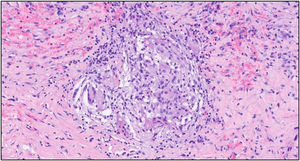

Histological examination revealed granulomas with multinucleated giant cells associated with lipid vacuoles, a fibrous stroma, lymphohistiocytic infiltration, and red blood cell extravasation (see Fig. 1).

Fig. 1.

Histological section of breast tissue from the first case.